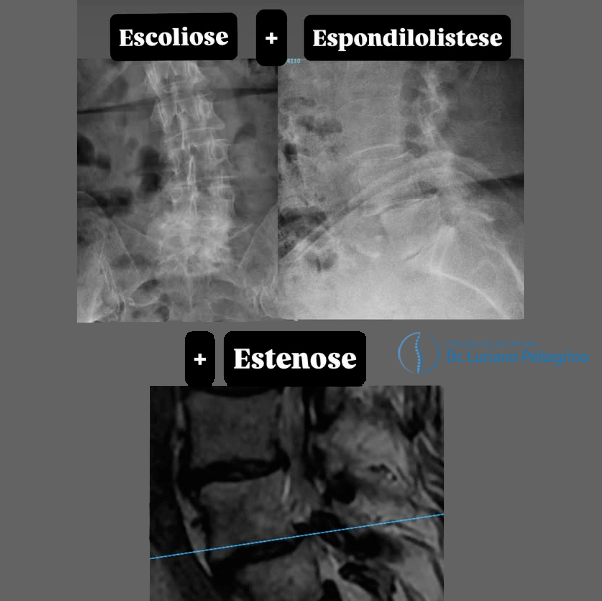

A dor na coluna (ou irradiada) decorre da compressão dos nervos na medula, causadas geralmente por:

- Estenose do canal vertebral;

- Espondilolistese;

- Deformidades na coluna.

A correção postural pode melhorar a mobilidade. Normalmente, o desalinhamento é provocado por: